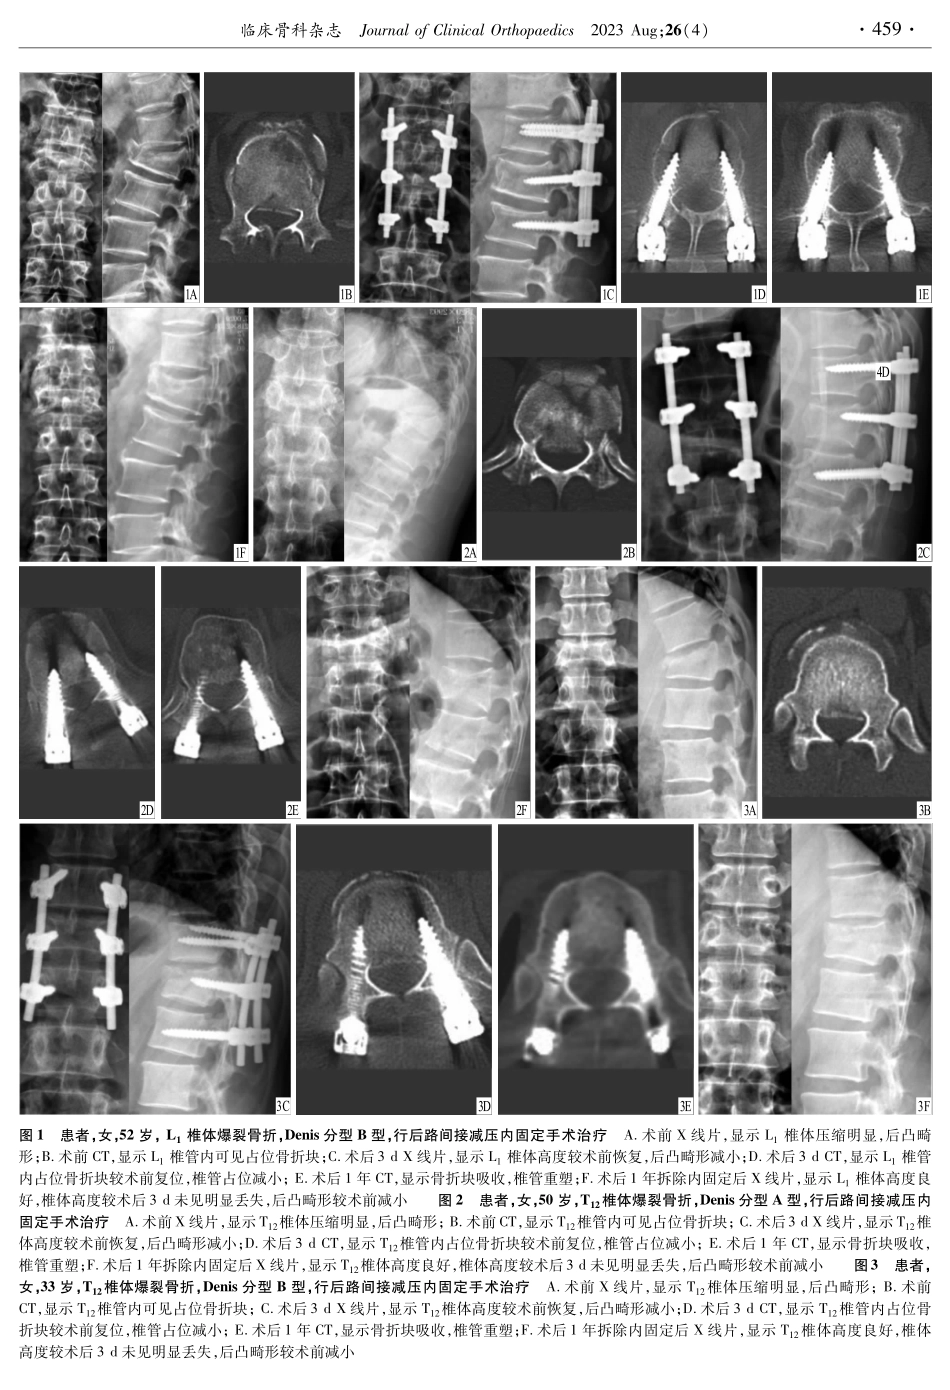

doi:10.3969/j.issn.10080287.2023.04.001·临床论著·后路间接减压内固定治疗胸腰椎爆裂骨折李招胜,朱大安,何勇摘要:目的探讨后路间接减压内固定治疗无神经损伤症状伴椎体后上缘骨折块的胸腰椎爆裂骨折的临床疗效。方法采用后路间接减压内固定治疗35例无神经损伤症状伴椎体后上缘骨折块的胸腰椎爆裂骨折患者。记录椎管占位率、椎体压缩率、Cobb角及并发症发生情况。结果患者均获得随访,时间12~18个月。无感染、断钉、迟发性神经损伤等并发症发生。术后3d及1年Cobb角、椎体压缩率、椎管占位率均较术前明显减小(P<005),术后1年与术后3dCobb角、椎体压缩率比较差异均无统计学意义(P>005),术后1年椎管占位率较术后3d减小(P<005)。结论对于无神经损伤症状伴椎体后上缘骨折块的胸腰椎爆裂骨折,通过后路间接减压内固定复位椎管占位骨折块并通过后期的椎管重塑,能够取得良好的临床疗效。关键词:胸椎;腰椎;脊柱骨折;椎体后上缘骨折块;内固定中图分类号:R6832;R6873文献标识码:A文章编号:1008-0287(2023)04-0457-04TheposteriorindirectdecompressionandinternalfixationfortreatmentofthoracolumbarburstfractureLIZhaosheng,ZHUDaan,HEYong(DeptofOrthopaedics,ShaoxingCentralHospital,Shaoxing,Zhejiang312000,China)Abstract:ObjectiveToinvestigatetheeffectofposteriorindirectdecompressionandinternalfixationforthoracolumbarburstfracturewithoutneurologicalinjurysymptomassociatedwithposterosuperiorfracturefragment.MethodsThe35patientswhoweresufferedfromthoracolumbarburstfractureswithoutneurologicalinjurysymptomassociate...